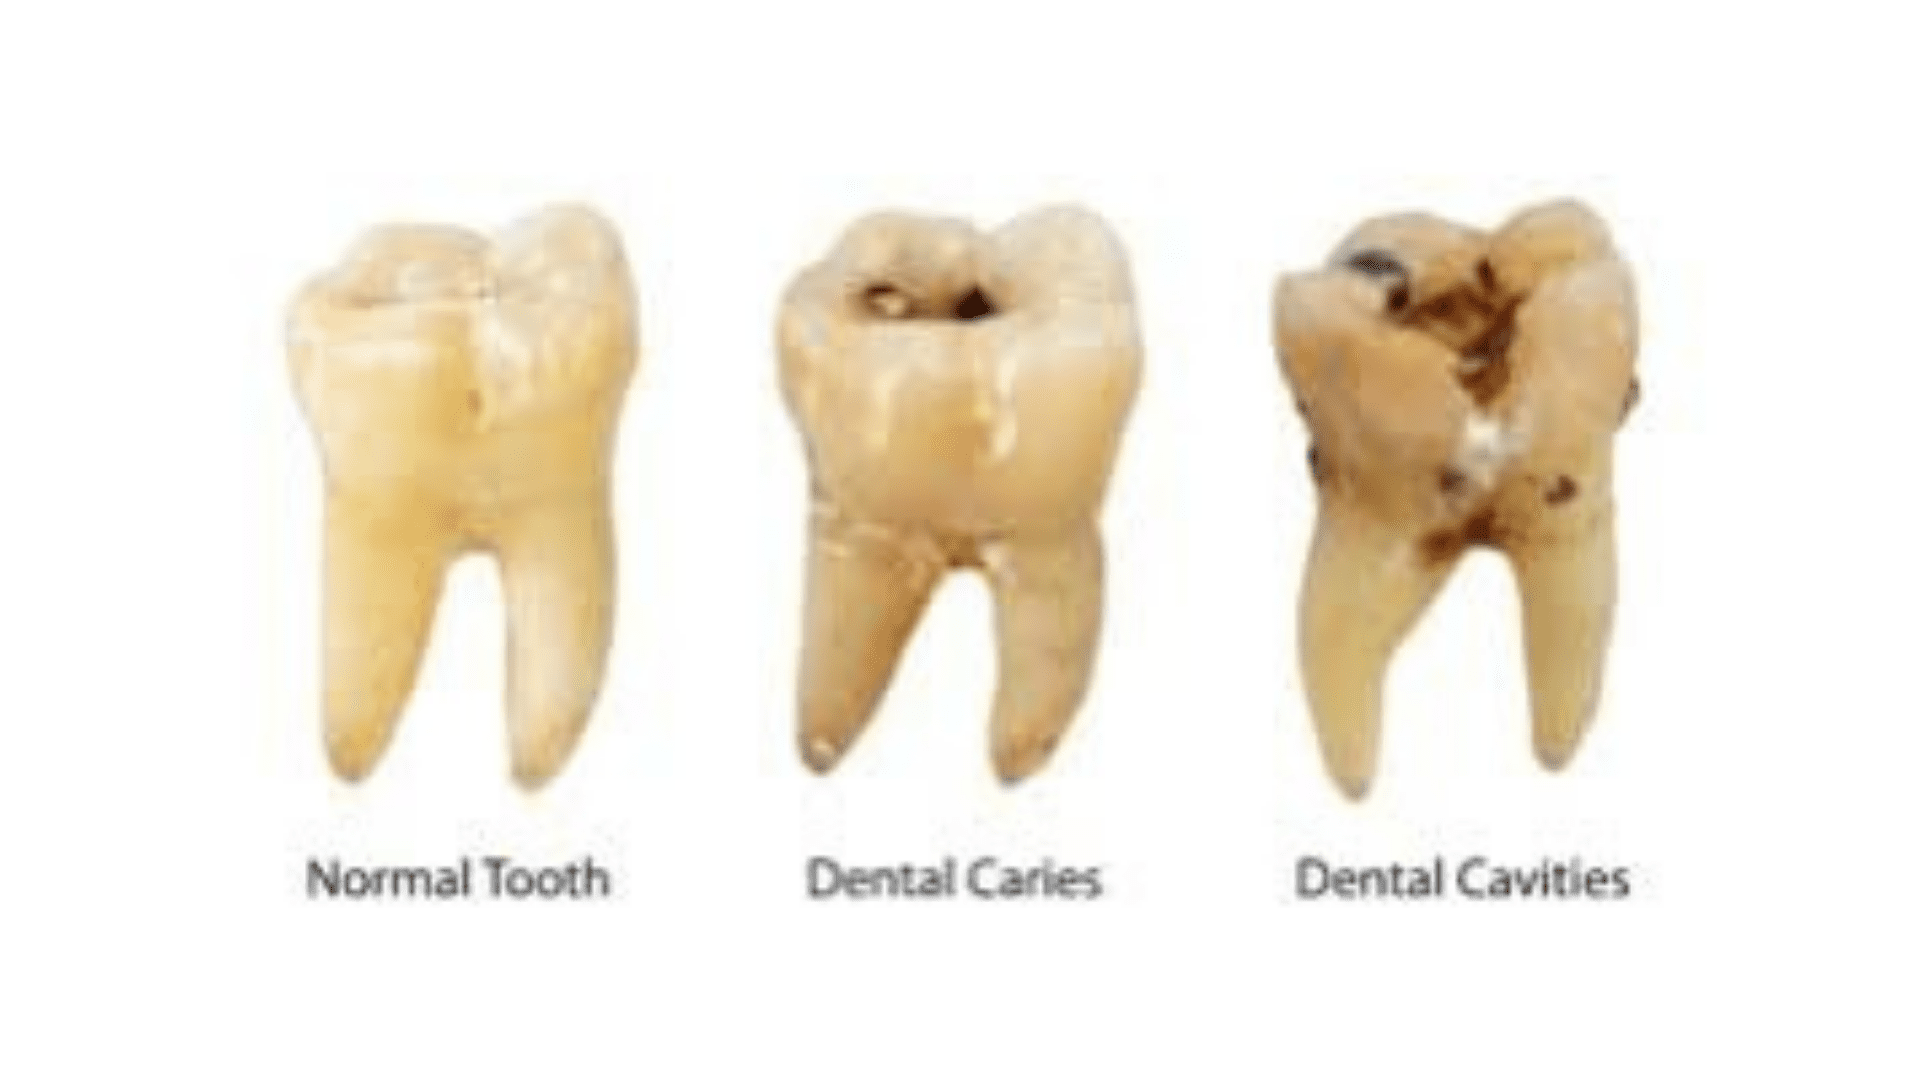

The risk of getting dental decay is not something that should be taken lightly. Cavities can appear unexpectedly, create a severe toothache, and essentially put your life on halt until they are treated. What is tooth decay, and what causes it? The food particles that remain in your mouth after you eat turn into plaque. Acid is produced when the bacteria in plaque break down the sugars and carbohydrates that are present in your mouth. This acid is powerful enough to soften and destroy the enamel, which is the outer coating of a tooth. This condition is known as dental decay, or a cavity. Stages, Symptoms, and Treatments of Tooth Decay

Because tooth decay has numerous stages, there are a variety of symptoms that you may see, feel, or even taste at times. The treatment you will require for your cavity will be determined by how serious the decay is and where it is located. Stage 1: The enamel is decaying. A cavity has not yet passed through the enamel, which is the outer coating of the tooth, during its early stages. During this period, symptoms are not very severe. In fact, you might not notice any of them at all. Sometimes, you may notice that your tooth has darkened, or you may feel a little sensitivity. Our Summerlin dentist will remove the area that has enamel decay and fill the empty space with a tooth-colored filling material in order to repair the decay. Fillings are a quick and inexpensive option that can last for many years. Stage 2: Dentin After the decay has passed through the enamel surface, it will reach the dentin layer. The dentin layer is fragile and is particularly susceptible to decay. This means that if the cavity reaches the dentin, it can spread quickly. During this stage, you will notice that your tooth sensitivity is more pronounced. You might feel uncomfortable when you eat sweets, clean your teeth, or are in chilly conditions. If the decay has impacted much of your tooth, our dentist in Summerlin may suggest that you get a crown instead of a filling. A crown is a hard cap that goes over your tooth and protects it from further harm. Because this treatment is more complex, it does take longer to finish. Additionally, it is more expensive than simply a basic filling. However, if crowns are manufactured and maintained correctly, they can last for many years, making your investment worthwhile. Stage 3: Pulp Chamber The decay will enter the pulp chamber once it has passed through the dentin layer. This is the section of the tooth that has blood arteries, nerves, and connective tissue. Your tooth will become infected after the cavity has reached the pulp. You will go through a lot of discomfort during this time. You may also start to feel uncomfortable due to heat, in addition to chilly weather. You may also experience persistent discomfort that necessitates the use of pain medication to alleviate it. We will take an x-ray of your tooth to make sure that the cavity has reached the pulp chamber. Root canal therapy will be necessary to fix and protect your tooth. This surgery consists of taking out the nerve tissue, cleaning the canals, and closing them off in order to stop bacteria from coming back in. You will probably need to be fitted for a crown in addition to receiving therapy on the nerves of your tooth. This will help to prevent additional harm to the tooth that is already at risk. Stage 4: Abscess The roots of your teeth are the parts that you cannot see when you look inside your mouth. They are located in the jaw. Nerve channels that go down each root extend beyond the pulp chamber. If your cavity has reached the nerves in the root of your tooth, you may have a terrible pain and swelling in your face. If you have an abscess, you will see a little bump on your gums, which is called a fistula. A dental abscess is a major medical issue. You might not find any relief from over-the-counter pain drugs. The toothache could prevent you from sleeping at night or cause you to wake up often. The gum tissue surrounding the tooth that is impacted may swell, and this swelling could migrate to your face. You might possibly develop a fever. If a cavity has caused a serious infection, it may not be possible to salvage the tooth with a root canal. It may be essential to do an extraction. We will be able to determine the state of your tooth and if it can be saved by using a dental x-ray. If it turns out that we need to take it out, a dental implant or a bridge could be a good option for you to replace it. Preventing Cavities Maintaining excellent dental hygiene is the most effective approach to avoid cavities. Make sure to have frequent cleanings and check-ups with your dentist in Las Vegas so that any problems can be addressed as soon as they arise. If you haven't gone to the dentist in a while or think you might have a cavity, you should make an appointment with Dr. Cohan at Summerlin Dental Solutions. Make an appointment by calling or book online today. GET TO KNOW YOUR BEST DENTIST IN SUMMERLIN